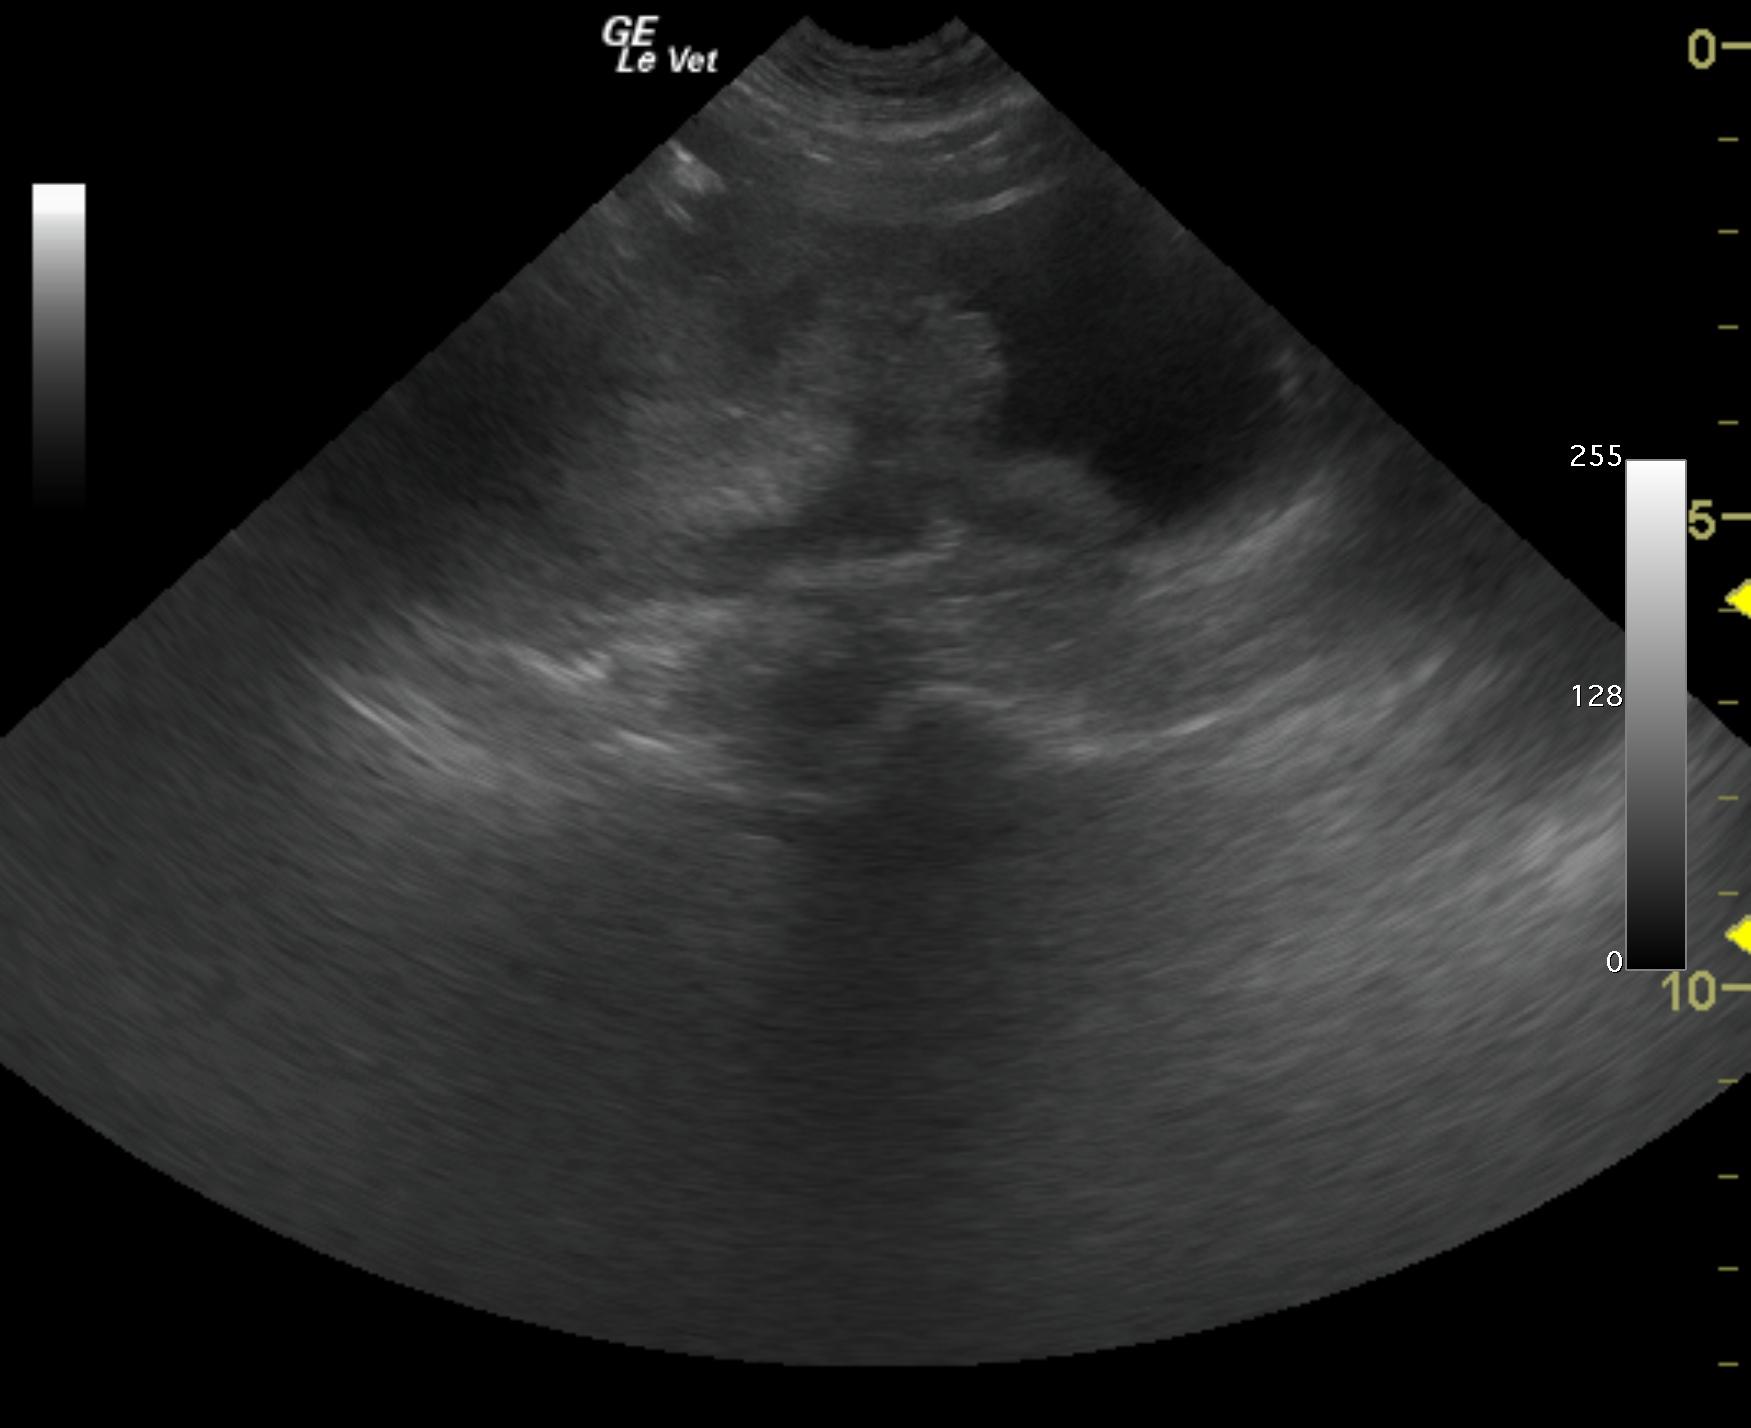

A 10-year-old female spayed German Shepherd Dog with a history of adenocarcinoma of the anal sac was presented for evaluation. Survey radiographs were suspicious for metastasis to the sublumbar lymph nodes.

A 10-year-old female spayed German Shepherd Dog with a history of adenocarcinoma of the anal sac was presented for evaluation. Survey radiographs were suspicious for metastasis to the sublumbar lymph nodes.